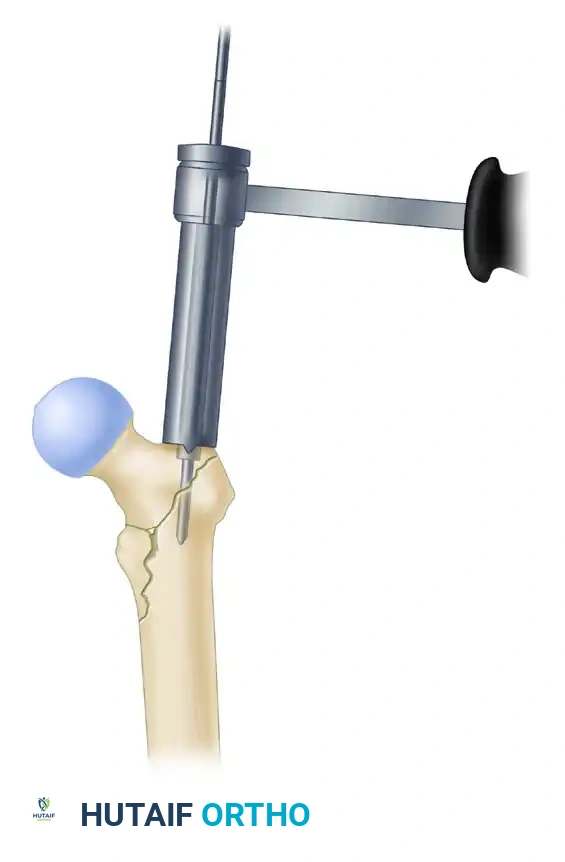

3. Proximal Reaming and Canal Preparation

- Once the guide pin is perfectly positioned, use the rigid proximal entry reamer to ream over the guide pin. Advance the reamer to a depth just below the level of the lesser trochanter.

- Crucial Step: Correct any residual malreduction before passing the ball-tip guide wire down the diaphysis. Reaming a malreduced femur will lock the fracture in a deformed position.

- Place a ball-tip guide pin down the shaft of the femur, advancing it to the level of the physeal scar (or the desired distal extent of the nail).

- Measure the guide pin using the radiographic ruler to determine the appropriate length of the intramedullary nail.

- We typically utilize a 10-mm diameter nail for standard intertrochanteric fractures. There is rarely a biomechanical benefit to placing a larger diameter nail in the elderly osteoporotic population, and attempting to force a larger nail significantly increases the risk of iatrogenic anterior cortical perforation or hoop stress fractures.

- Ream the diaphyseal canal sequentially to a diameter 1.5 mm larger than the selected diameter of the intramedullary nail.